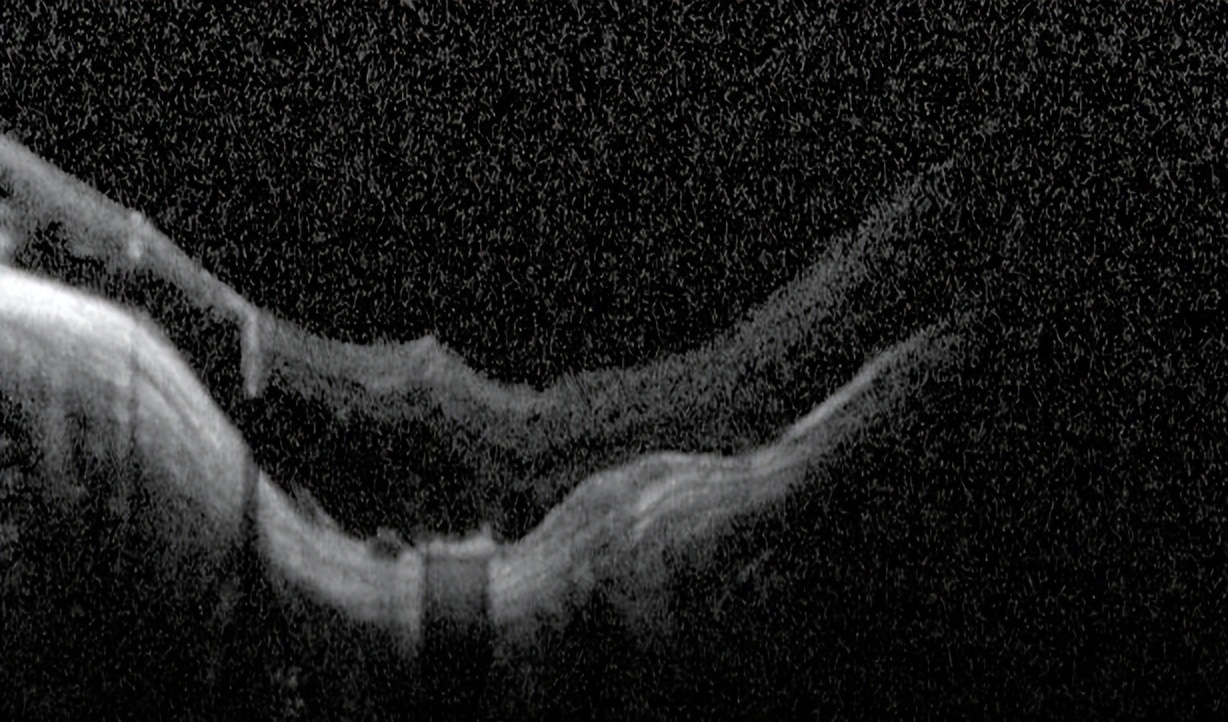

我检查以后发现他双眼的裸眼视力都非常差,右眼只有50公分数指,左眼只有0.02,矫正视力右眼戴2000度眼镜勉勉强强可以看0.05,左眼戴1900度眼镜也只能勉勉强强看到0.15,双眼晶状体轻度浑浊,玻璃体浑浊。最令我吃惊的是老人家双眼黄斑区视网膜不仅萎缩得像一张薄纸,而且还有劈裂性脱离及视网膜下陈旧性疤痕形成。

右眼手术以前眼底(萎缩、劈裂性脱离及视网膜下陈旧性疤痕)

左眼手术以前底(萎缩、劈裂性脱离及视网膜下陈旧性疤痕)